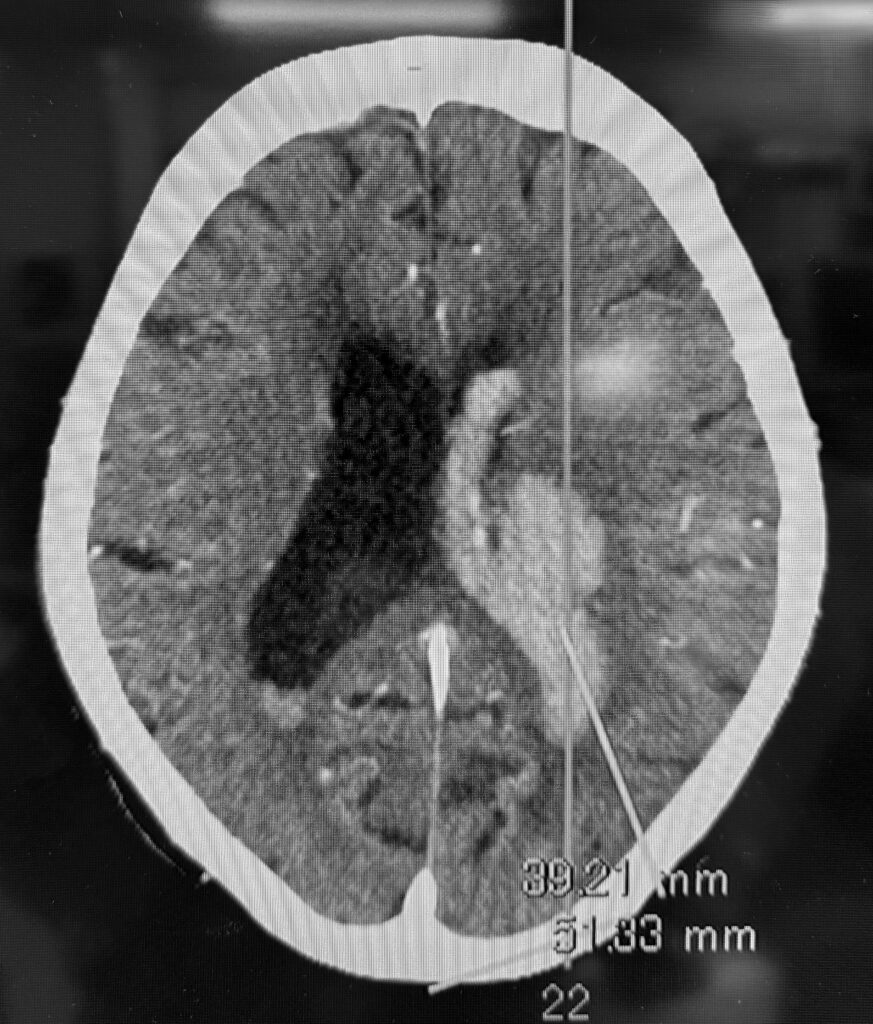

視床出血、脳室穿破の症例で、患者さんはご高齢なので内視鏡で低侵襲に血腫除去したいという要望でした。ご要望にお応えし、局所麻酔で3センチ切開し、1センチの穴を開けて血腫除去してきました。無事に血腫は取れたので今頃はリハビリテーションに励んでいることでしょう。

私は上記の写真のように個別にアプローチを決定し、透明シースを挿入し、内視鏡下に血腫除去する方法で良好な結果を得ています。ただし、エビデンスとなるとある程度の症例数を複数施設でまとめて、評価ポイントも決めて、別の治療方法との差を出して決まるので難しいです。

ひとまずオーソドックスな職人技で上記写真のように血腫除去して帰ってきました。